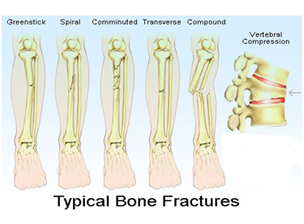

There are several different ways in which a bone can fracture; for example a clean break to the bone that does not damage surrounding tissue or tear through the skin is known as a closed fracture or a simple fracture. On the other hand, one that damages surrounding skin or tissue is known as a compound fracture or an open fracture. Compound or open fractures are generally more serious than simple fractures, with a much higher risk of infection.

A fracture, also referred to as a Bone fracture, FRX,FX, Fx or #, is a medical condition where the continuity of the bone is broken. There are several different ways in which a bone can fracture; for example a clean break to the bone that does not damage surrounding tissue or tear through the skin is known as a closed fracture or a simple fracture. On the other hand, one that damages surrounding skin or tissue is known as a compound fracture or an open fracture. Compound or open fractures are generally more serious than simple fractures, with a much higher risk of infection.

There are several different ways in which a bone can fracture; for example a clean break to the bone that does not damage surrounding tissue or tear through the skin is known as a closed fracture or a simple fracture. On the other hand, one that damages surrounding skin or tissue is known as a compound fracture or an open fracture. Compound or open fractures are generally more serious than simple fractures, with a much higher risk of infection.  The period immediately after a bone fracture is critical for the proper repair of the bone and healing of the affected tissues. Bones begin to heal very quickly after a fracture and the bone tissue will knit together with any nearby bone fragments to form a callus of cartilage and eventually new bone tissue.

A fracture, also referred to as a Bone fracture, FRX,FX, Fx or #, is a medical condition where the continuity of the bone is broken. There are several different ways in which a bone can fracture; for example a clean break to the bone that does not damage surrounding tissue or tear through the skin is known as a closed fracture or a simple fracture. On the other hand, one that damages surrounding skin or tissue is known as a compound fracture or an open fracture. Compound or open fractures are generally more serious than simple fractures, with a much higher risk of infection.

There are several different ways in which a bone can fracture; for example a clean break to the bone that does not damage surrounding tissue or tear through the skin is known as a closed fracture or a simple fracture. On the other hand, one that damages surrounding skin or tissue is known as a compound fracture or an open fracture. Compound or open fractures are generally more serious than simple fractures, with a much higher risk of infection.  The period immediately after a bone fracture is critical for the proper repair of the bone and healing of the affected tissues. Bones begin to heal very quickly after a fracture and the bone tissue will knit together with any nearby bone fragments to form a callus of cartilage and eventually new bone tissue.